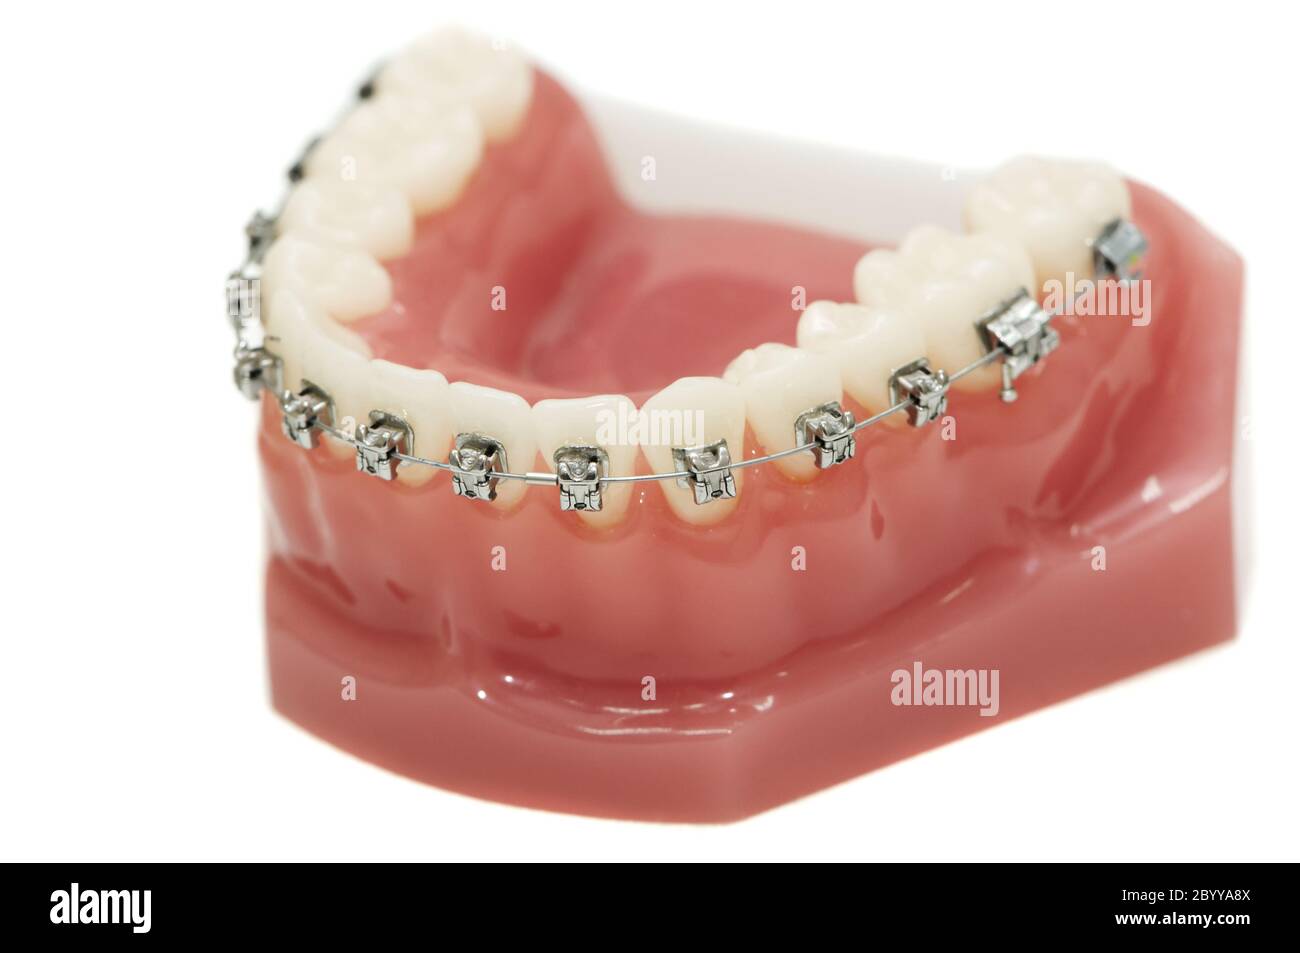

modèle de support de mâchoire inférieure isolé Banque D'Imageshttps://www.alamyimages.fr/image-license-details/?v=1https://www.alamyimages.fr/modele-de-support-de-machoire-inferieure-isole-image361403866.html

modèle de support de mâchoire inférieure isolé Banque D'Imageshttps://www.alamyimages.fr/image-license-details/?v=1https://www.alamyimages.fr/modele-de-support-de-machoire-inferieure-isole-image361403866.htmlRM2BYYA8X–modèle de support de mâchoire inférieure isolé